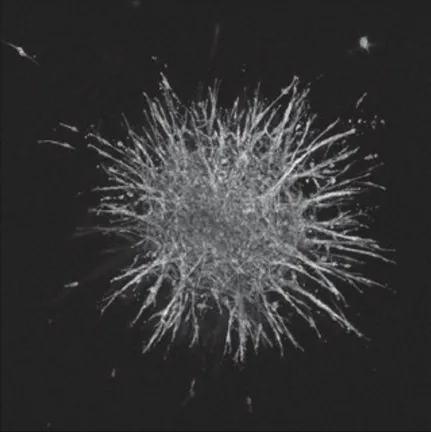

00 Ultrasound Guidance